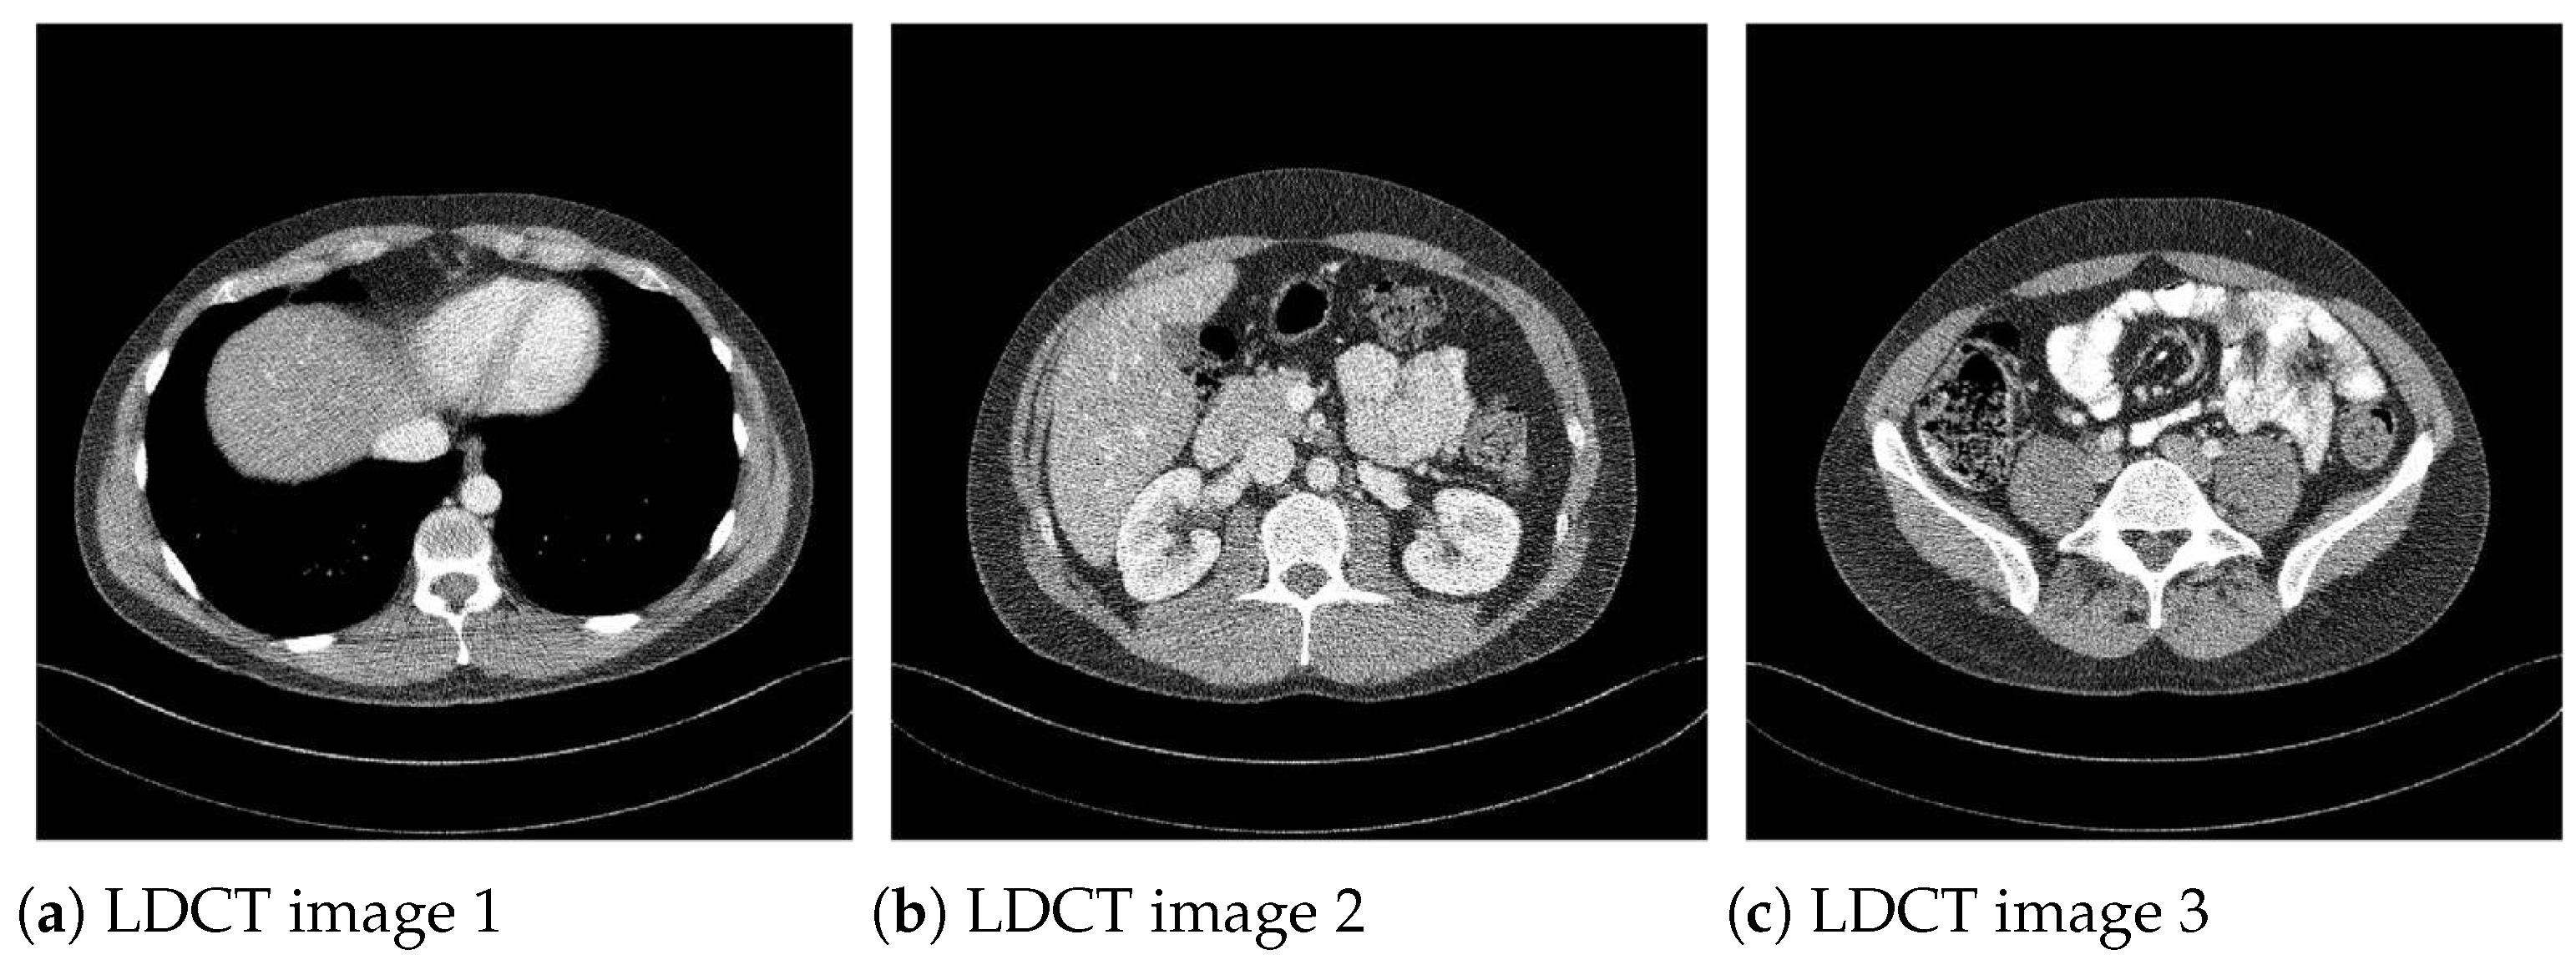

Algorithms Free FullText Impact of Iterative Bilateral Filtering Pitch And Noise Ct In this poster we wish to provide information leading to correct guidance in the. Pitch = table travel per gantry rotation (mm) / total nominal beam width, or pitch = table travel per. Comparing the level of desired signal (photons) to the level of. Current misconceptions concerning pitch & dose. Pitch is calculated as follows: Noise in ct is measured. Pitch And Noise Ct.